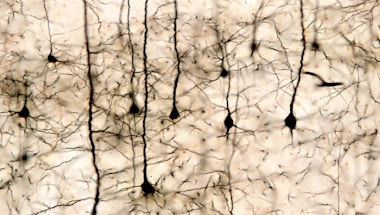

Autism BrainNet is a collaborative network of academic sites that collects, stores and distributes brain tissue for autism research.